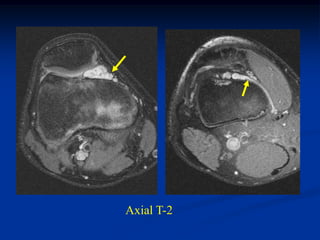

Case #273       Axial T-1 MRI

11 year male

lipoma

deltoid muscle

Coronal T-1 MRI